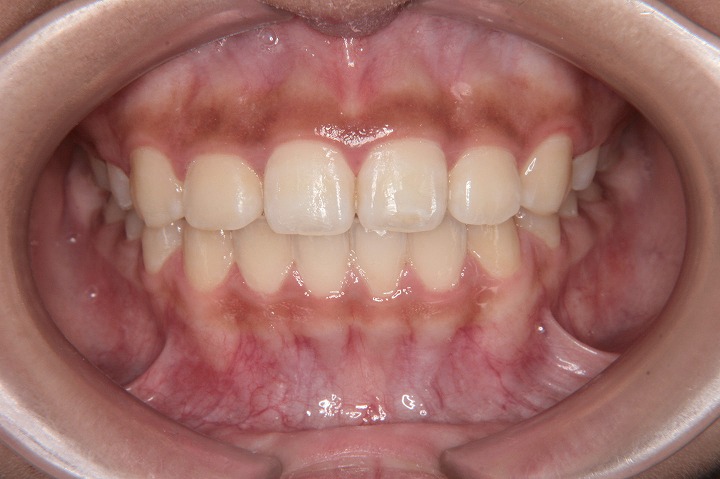

トップページ > 症例紹介 > 13歳 女性 永久歯列 抜歯 (抜歯部位:上下顎小臼歯)

歯のデコボコと口元の突出感を主訴に来院された中学1年生の患者さんです。叢生と上下顎前歯の外側への傾斜を認めたため、Eライン改善のため上下顎小臼歯抜歯ケースとしてでエッジワイズ装置を用いて配列を行っております。

初診時

動的治療終了時